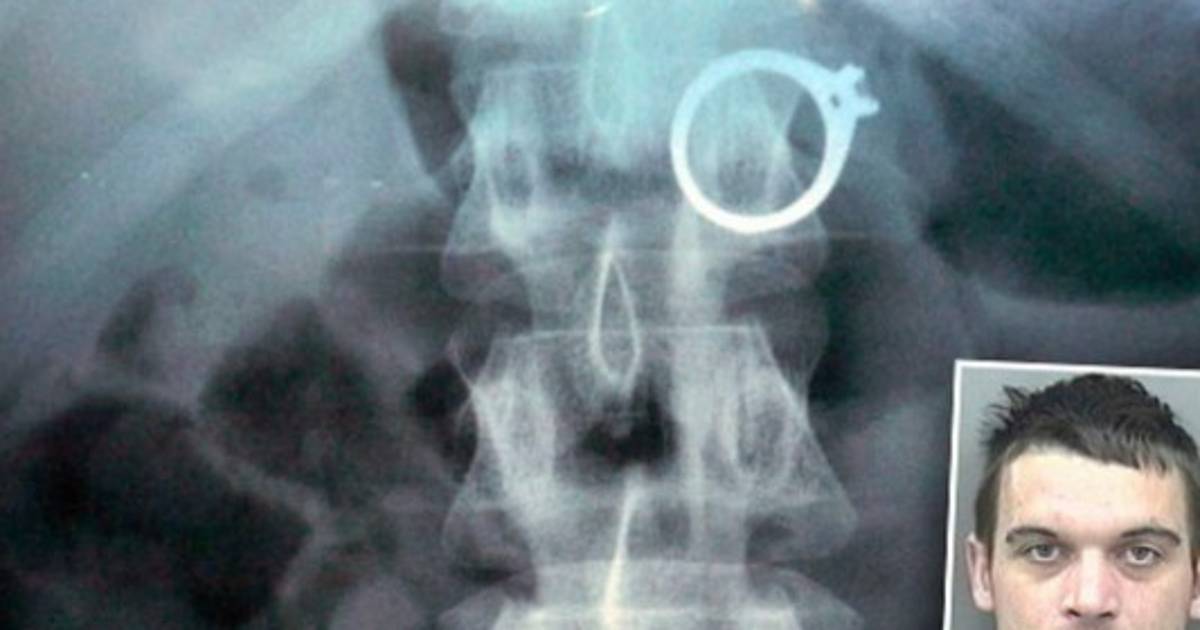

1. Simon Hooper se tragó un anillo. Resulta que el joven inglés quería el mejor anillo de compromiso para su novia, pero al saber el precio de la joya y no poder pagarlo, decidió tragárselo. Por su acción terminó en la policía y luego en el hospital para que se lo retiraran del estómago. 04/12/2019 - 00:001 / 10 -